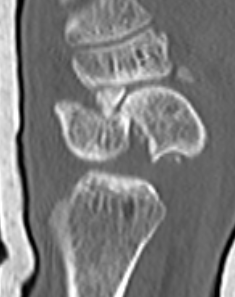

Scaphoid waist fracture 1 mm displaced

Scaphoid fracture with significant displacement

Scaphoid proximal pole fracture